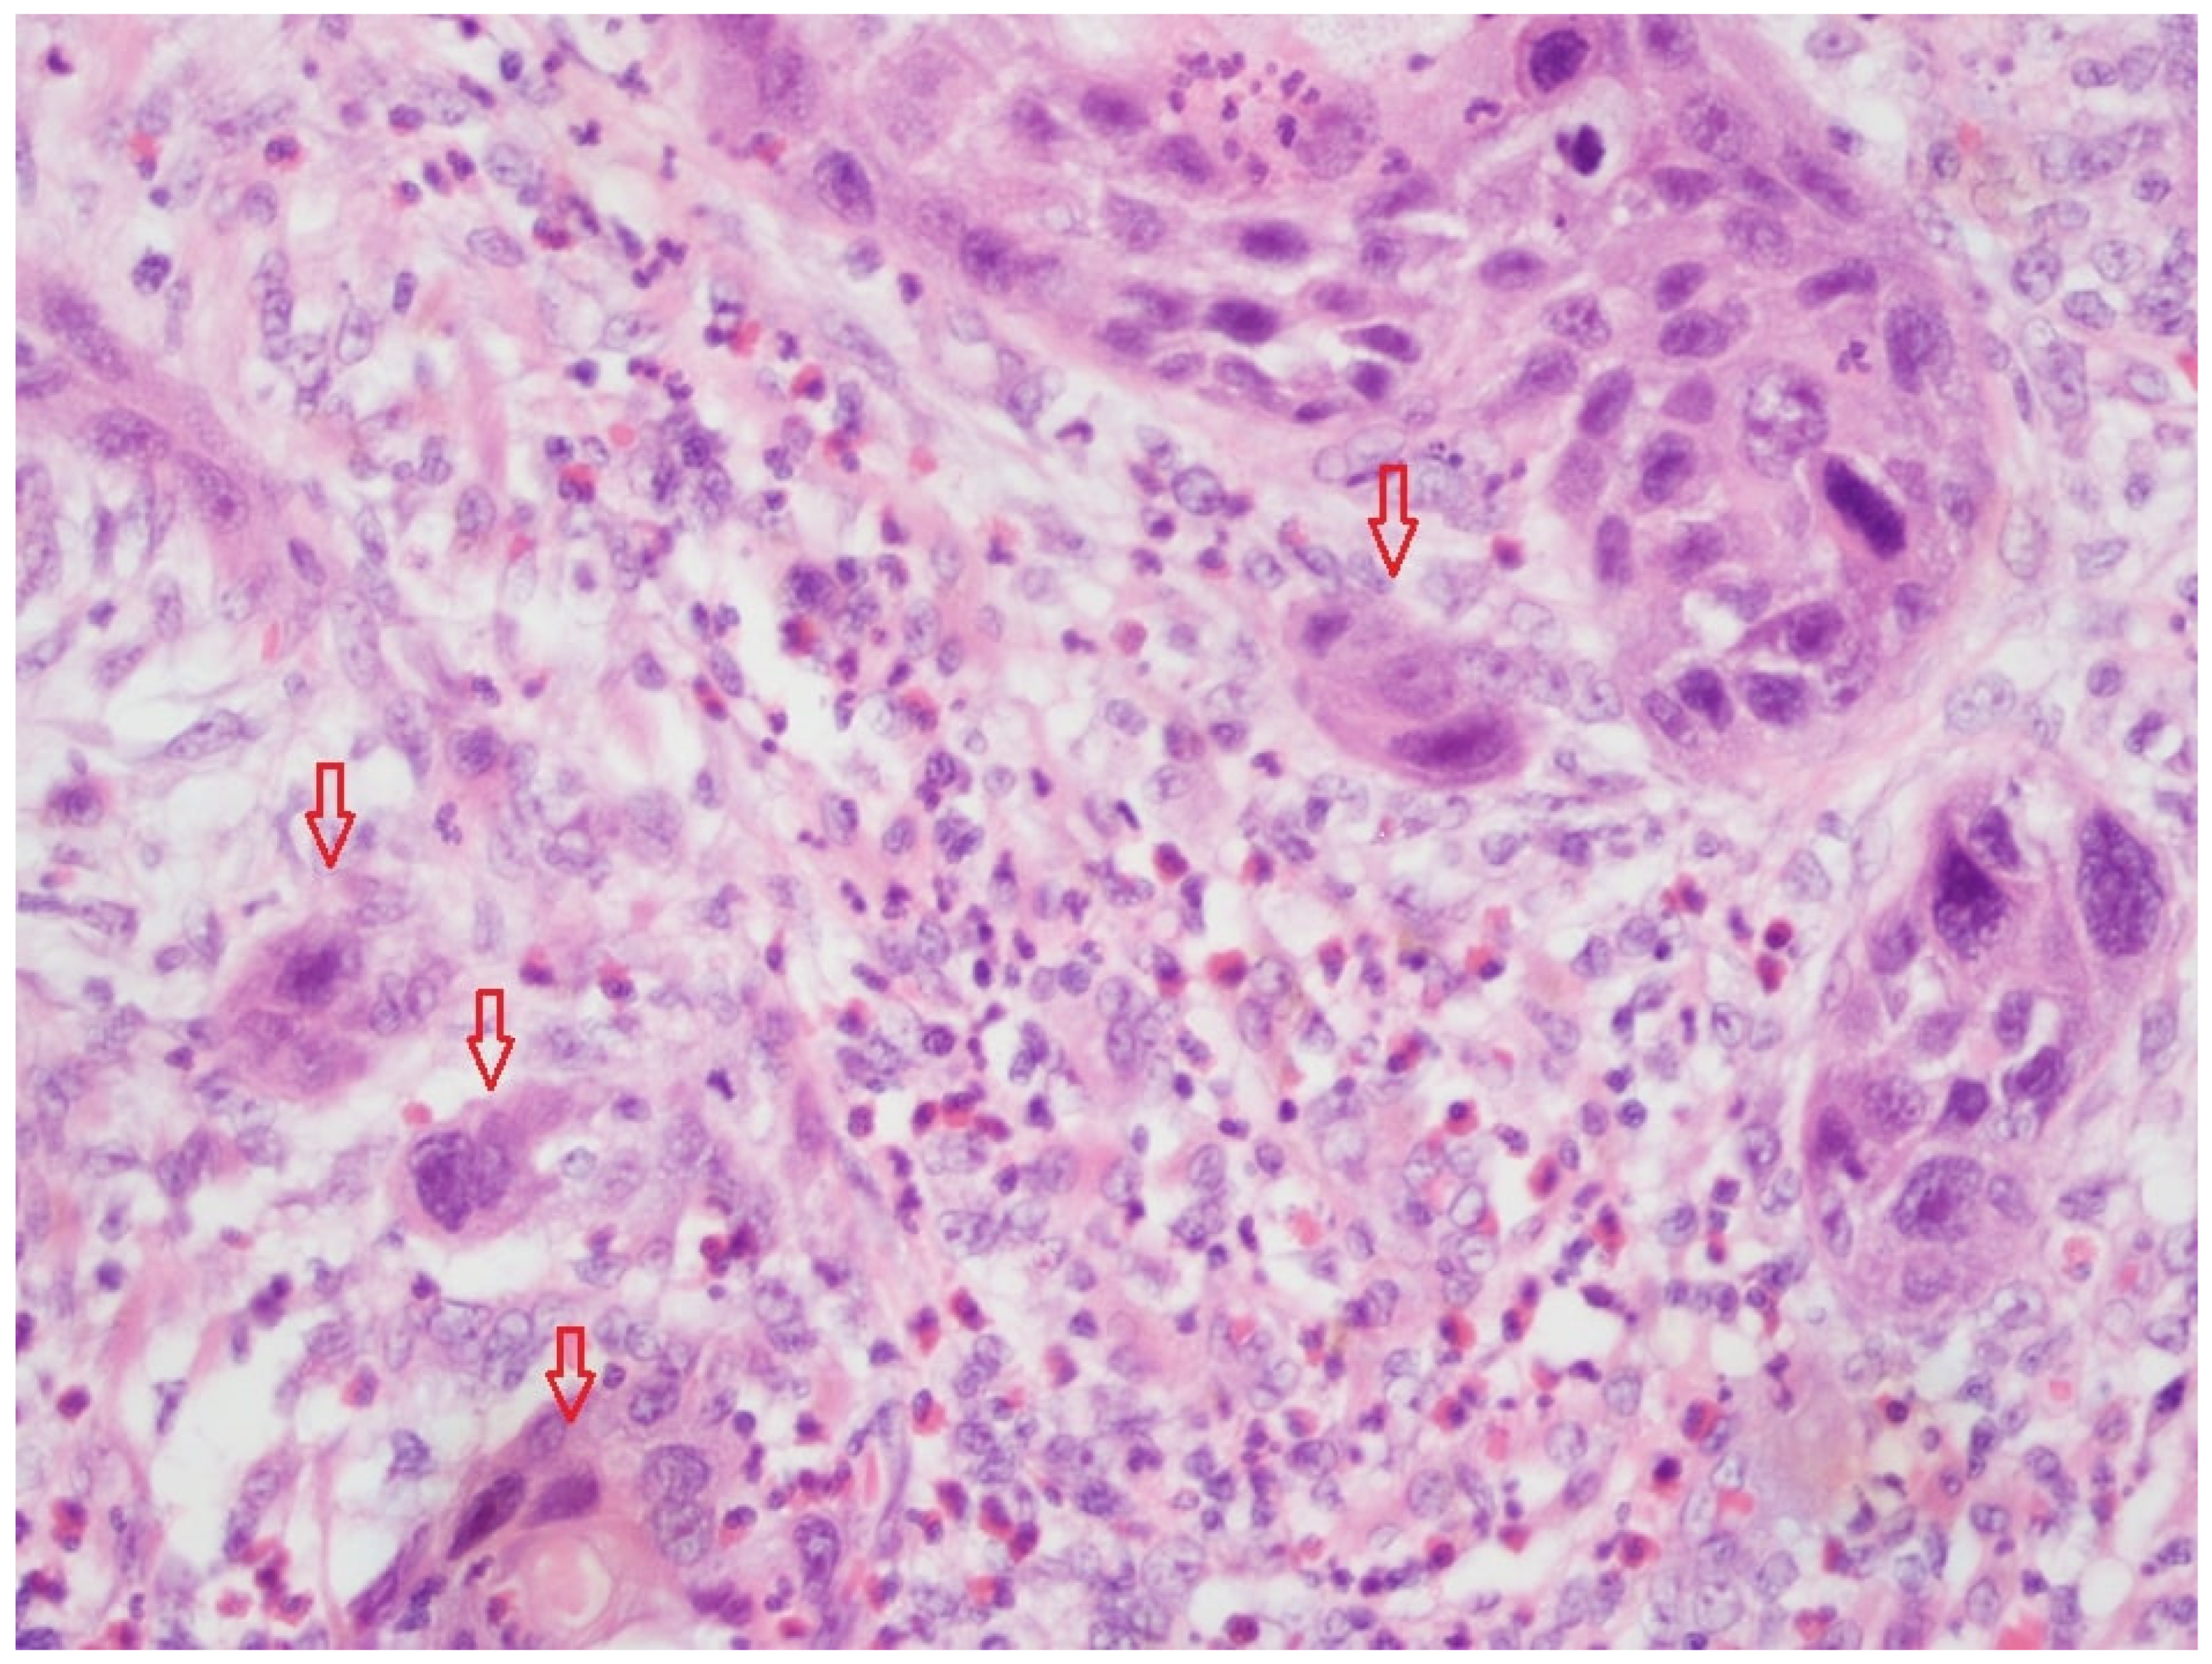

Figure 1 shows tumor budding in a FFPE-fixed tissue slide (HE, magnification 20×). The high-power field (HPF) presented a low TB, and thus, a TB score of 1.

Figure 1. Example section of FFPE-fixed HNSCC tissue (HE, magnification 20×) with tumor budding. The tumor budding with a tumor cell nest (<4 cells; red arrows) is clearly visible on the left-hand side and upper right-hand side. This HPF presented low tumor budding (TB score 1).